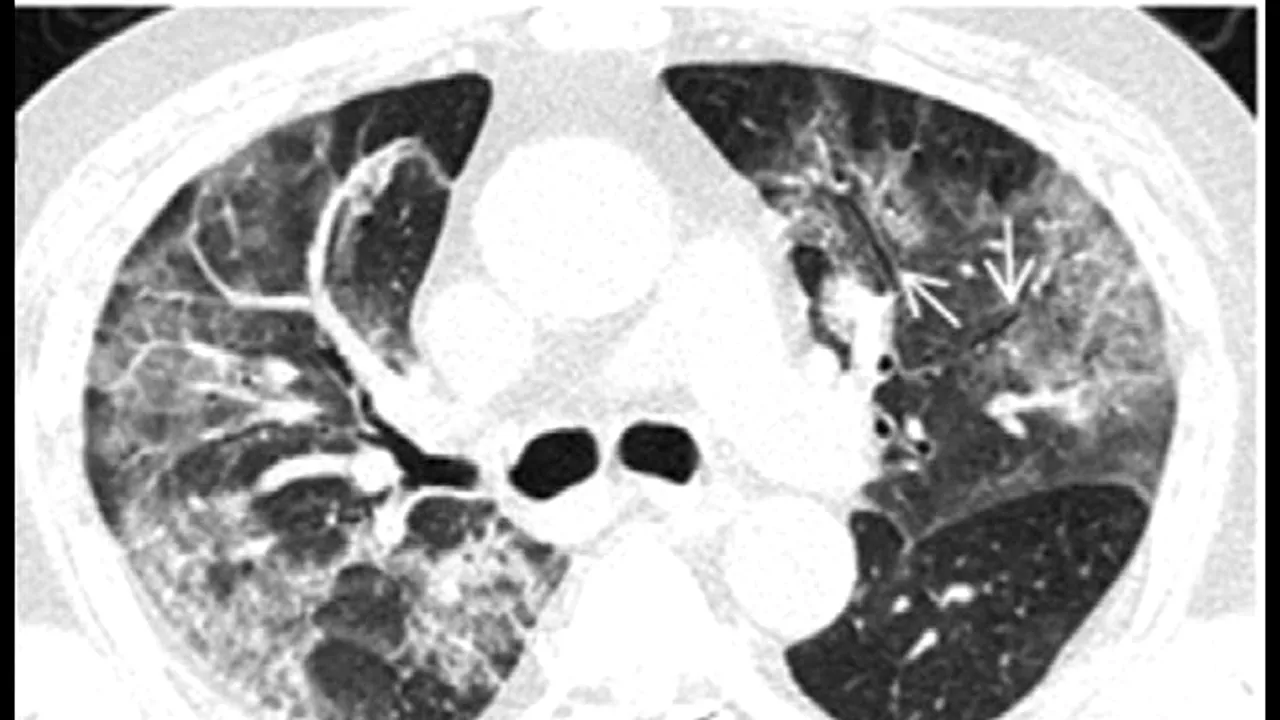

Pacienții cu cazuri severe dezvoltă de obicei lichid în plămânii lor, similar cu cele observate în cazurile pneumonice standard. Fluidul respectiv poate fi detectat pe un tomograf, unde apare sub formă de petice albe pe care medicii le numesc „sticlă măcinată”.

În mod normal, plămânii sănătoși apar ca fiind de culoare negru pe tomografie.

„Seamănă cu o sticlă mată măcinată care, de fapt, reprezintă fluid în spațiile pulmonare”, a explicat Paras Lakhani, radiolog la Universitatea Thomas Jefferson, pentru Business Insider.

Însă leziunile sunt foarte grave dacă se extind până la marginile plămânilor pacientului, a mai adăugat radiologul..

„Așa ceva nu întâlnim prea des. Am văzut astfel de leziuni în cazul pacienților bolnavi de sindromul respirator acut sever (SARS) în cazul celor bolnavi de sindromul respirator din Orientul Mijlociu (MERS)”, a declarat Paras Lakhani pentru sursa citată.